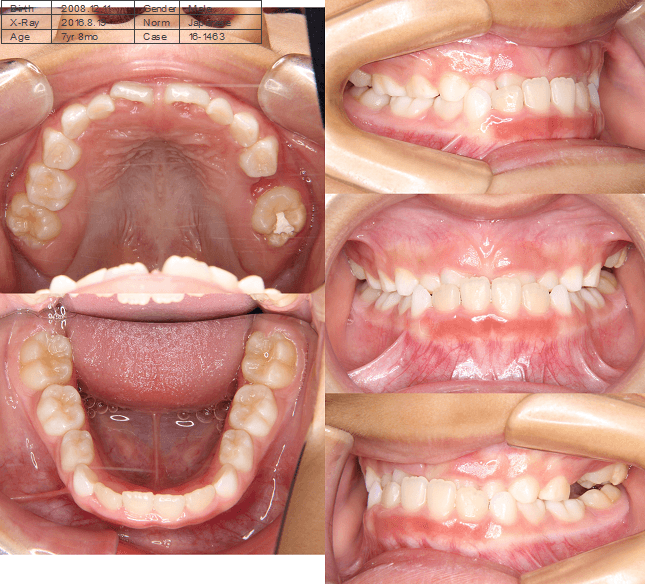

早期矯正治療 開咬症例

主訴 | 前歯がしっかり噛み合わず、食事時に違和感を覚えて来院された患者様です。 |

---|---|

診断結果 | 6歳6か月の女児。 上下の前歯が接触せず隙間があり、開咬と診断されました。 |

治療内容 |

|

治療後の経過 | 1年11か月間の動的治療により、前歯の噛み合わせが改善されました。現在は3〜4か月ごとに定期検診を行い、上下顎の骨の成長や永久歯の萌出状況を確認しながら、本格矯正治療のタイミングを検討しています。 |

治療期間 | 動的治療期間:1年11か月 治療回数:18回 |

治療費用 | 400,000円(税別) |